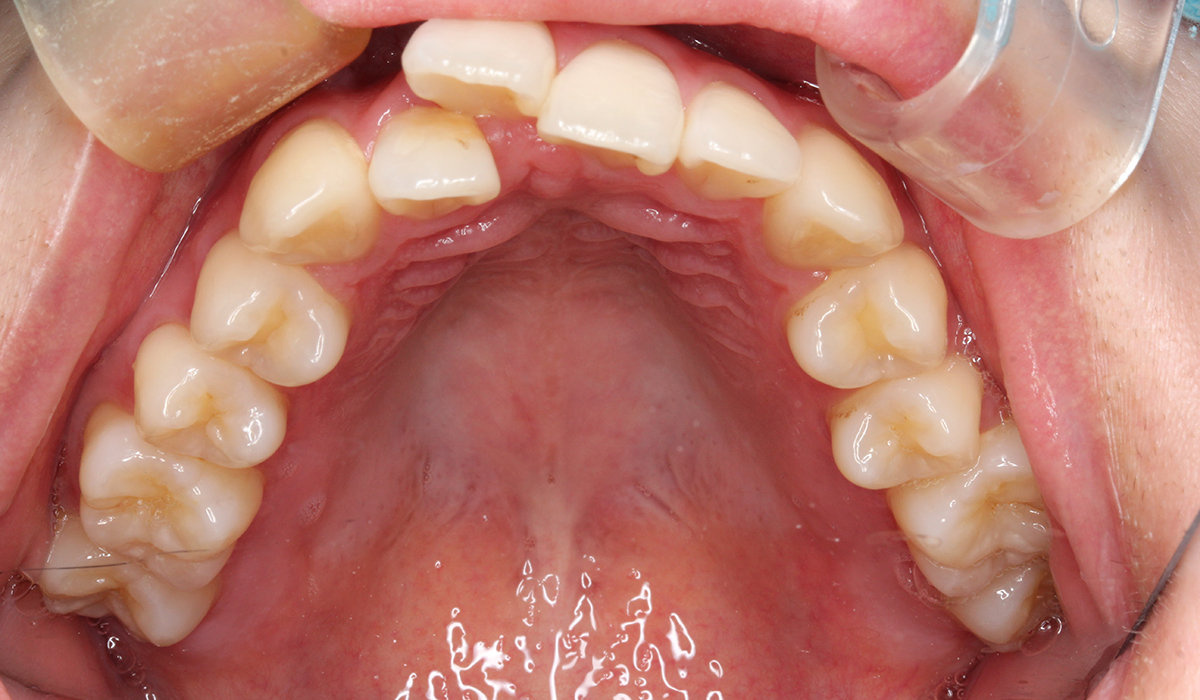

上顎

術前

BK終了時

術後